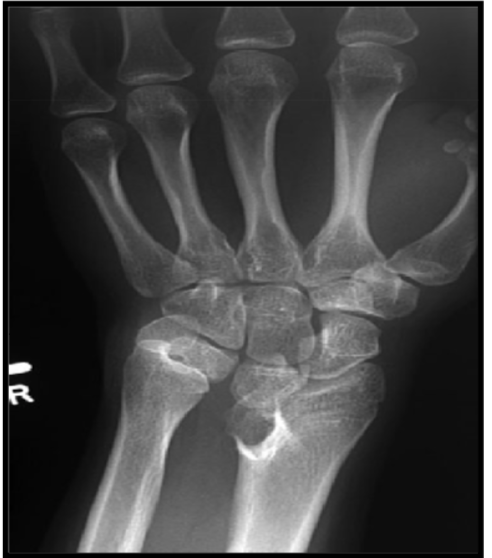

Madelung’s deformity

anat deformation anatomique